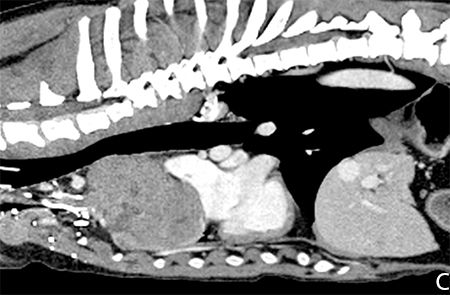

CT and fine-needle aspirates or core biopsies are helpful in differential diagnosis but flow cytometry may improve the. Thymoma is an uncommon canine and feline neoplasm of thymic epithelial cells. Thymoma is a tumor of the thymus gland which is part of your dogs lymph system. Thymic tumors usually affect older animals with a mean age of 9 to 10 years although one case of a 1-year-old pug has been described. You can see tissue and bone much better in person when viewing these X-rays with the naked eye. In the presented case series the median age at presentation was 10 years and.

Interestingly mice with thymic tumor displayed highly enlarged spleen which seemed to be histologically disorganized Fig. The risk of TLS needs to be evaluated in dogs with the tumors containing radiosensitive components and treated with RT such as thymoma. Thymoma in an 11-year-old dog. Middle-aged or older dogs can be affected and no sex predilection exists. 75 response rate in cats and dogs with thymomas including 20 CR.

Thymoma in Dogs. Pneumonitis and pericarditis Chemotherapy. Thymus being one of the primary lymphoid organs we also investigated the immune compartment notably thanks to spleen analysis. Thymoma in an 11-year-old dog. Rated 4 out of 5 based on 1 customer rating.